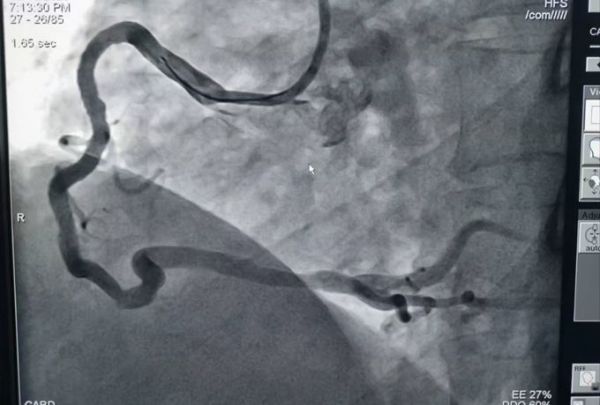

术后造影

“你的另一支血管也必须接受手术……”27日,按照出院前医生的建议,冯先生再次来到心内3病区准备接受第2次手术。在谭利国主任团队的紧密合作下,手术历时2个小时顺利完成。术后,冯先生在ccu观察一天后,转入普通病房。几天后,顺利出院。